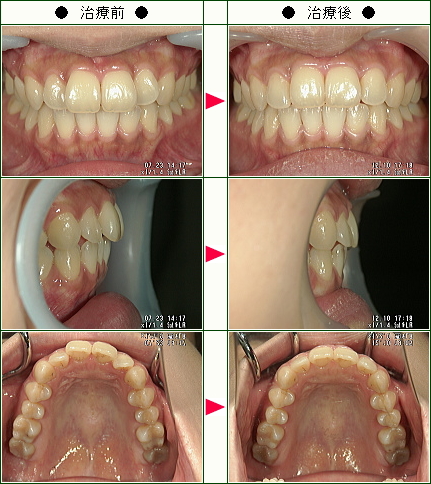

☆歯のデコボコ矯正症例(M様 31歳 女性)